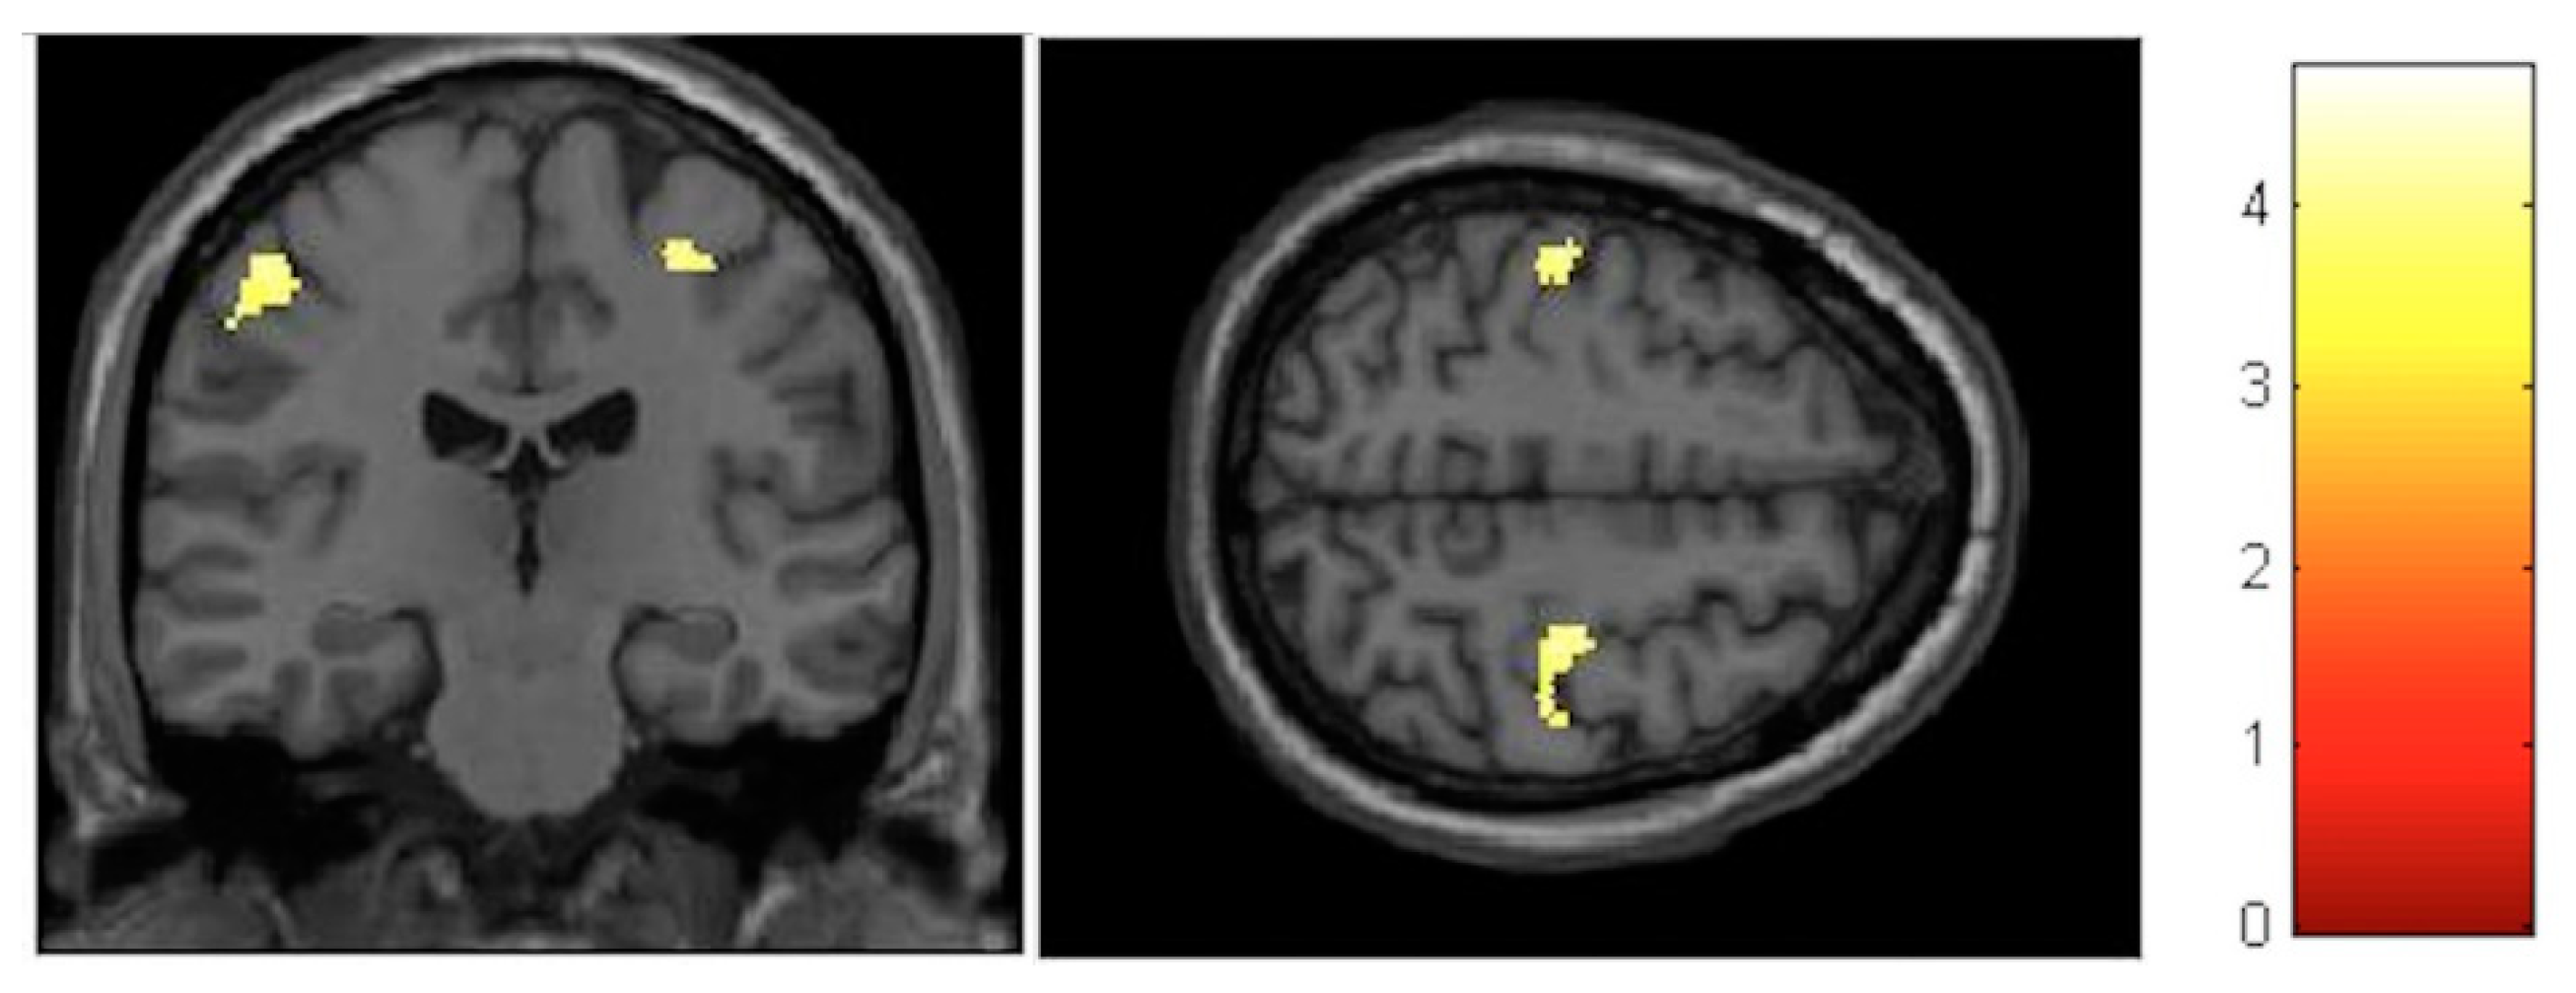

| Effect | Brain Region | Left Hemisphere MNI Coordinates (Cluster Size in Voxels) | T | d | Right Hemisphere MNI Coordinates (Cluster Size in Voxels) | T | d |

|---|---|---|---|---|---|---|---|

| Increment | Paracentral | −9, −32, 59 (1298) | 5.93 | 0.41 | 14, −36, 63 (1589) | 5.47 | 0.40 |

| Increment | Hippocampus | 34, −16, −11.5 (20) | 3.85 | 0.36 | |||

| Decrement | Insula | −32, −10, 12 (60) | 3.91 | 0.36 | 35, −20, 18 (261) | 4.36 | 0.38 |

| Decrement | Putamen | −20, 14, 0 (1879) | 5.45 | 0.40 | 24, 11, 2 (137) | 4.13 | 0.37 |

| Decrement | Cerebellum | −12, −47, −21 (511) | 5.33 | 0.40 | 11, −47, −23 (262) | 4.06 | 0.37 |